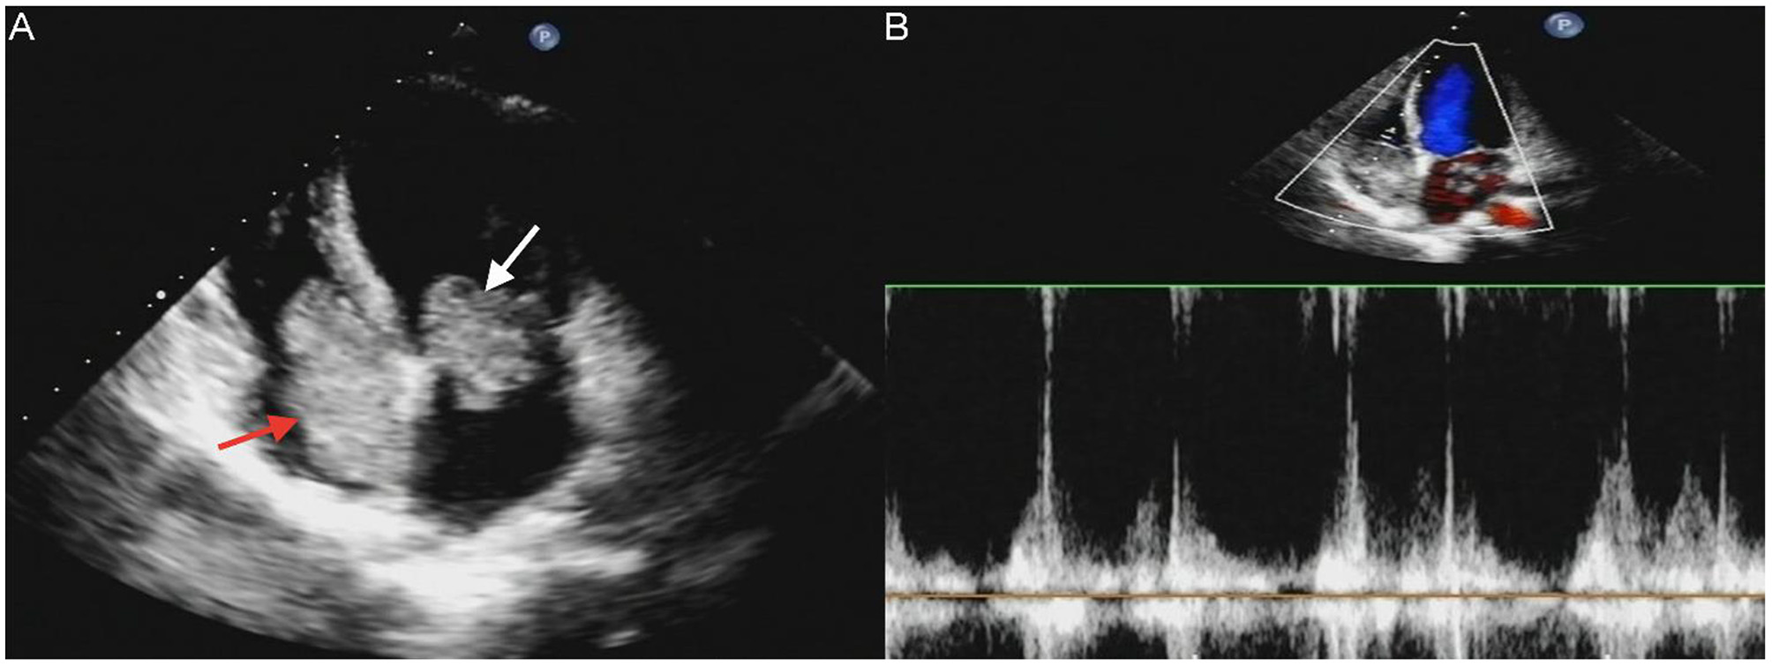

Figure 2

Transthoracic echocardiography (TTE) revealed masses attached to the atrial septum in the left atrial cavity (white arrow) and the right atrial cavity (red arrow) (A). Acceleration of tricuspid valves antegrade flow (B).

A 17-year-old girl presented to our hospital on August 22, 2021 with clouding of consciousness for more than 3 days. At 3+days prior, the patient was unable to speak the patient was unable to speak when called softly and unable to open the right eye, combined with involuntary movements of the limbs and incontinence. The patient visited the local hospital immediately, where relevant tests were performed, suggesting intracranial lesions. Since the specific treatment measures were unavailable at the previous hospital, she was transferred to our hospital for further treatment. There was no history of trauma or familial genetic diseases, such as high blood pressure and diabetes. Physical examination revealed a body temperature of 37.0°C, heart rate of 110 bpm, regular heart rhythm, blood pressure of 113/77 mmHg, and no pathological murmurs in the valve region; pulmonary auscultation revealed coarse rales in the entire lung. The pupils were equal, round, and pupillary light reflexes were delayed. Both lower limbs exhibited hypertonia and hyperreflexia of the knee and tendon reflexes. Laboratory examinations revealed the following levels (normal range): coagulation function test showed D-dimer was 0.57 mg/L (< 0.5 mg/L) and fibrinogen was 5.82 g/L (2.00–4.00 g/L). Routine blood tests showed that the absolute value of neutrophils was 7.38 × 109/L (1.8 × 109/L−6.3 × 109/L). Infection-related markers showed that the hypersensitive C-reactive protein level was 111.563 mg/L (0.068–8.200 mg/L). Creatine kinase, α-hydroxybutyrate dehydrogenase, and lactate dehydrogenase levels were 148 U/L (26–140 U/L), 218 U/L (90–180 U/L), and 295 U/L (140–271 U/L), respectively. Computed tomography pulmonary angiography (CTPA) detected filling defects in the right atrium, left atrium, and left lower pulmonary basilar artery (Figure 1), and a diagnosis of Pulmonary embolism was made. Transthoracic echocardiography (TTE) revealed irregular iso-echoic masses in the bilateral atrium that were likely myxomas, given their location and appearance in a young patient; the myxoma in the left atrium measured approximately 38 × 21 mm, and it was attached to the junction of the lower part of the interatrial septum (IAS) and the root of the anterior mitral leaflet; in the right atrium it measured approximately 51 × 27 mm, and it was attached to the lower part of the IAS (Figure 2A). These masses resulted in the acceleration of the tricuspid valve antegrade flow (Figure 2B). Craniocerebral computed tomography (CT) showed extensive hypodensity in the bilateral parts of the pons and patchy hypodensity in the left corona radiata area and bilateral basal ganglia areas. Magnetic resonance imaging (MRI) also revealed extensive hypointensity on T1-weighted imaging and hyperintensity on T2-weighted imaging in the bilateral parts of the pons, and a patchy hyperintensity on T2-weighted imaging in the bilateral basal ganglia areas; bilateral centrum semiovale; and right frontoparietal lobe, which presented as high signal on diffusion-weighted imaging (DWI) (Figure 3). This confirmed the diagnosis of brain ischemia. To prevent thrombosis, low molecular weight heparin calcium (subcutaneous injection, 0.4 ml/12 h) was commenced on the second day of admission and continued until discharge. The patient underwent successful removal surgery for a biatrial myxoma. The masses were sent for histological examination, which confirmed the presence of a myxomatous matrix containing myxoma cells (Figure 4). The patient recovered uneventfully and was discharged 9 days after the procedure. The patient has been followed-up postoperatively for over 2.5 months, and limb motor function of the patient has recovered to some degree, but there is intellectual and cognitive decline.